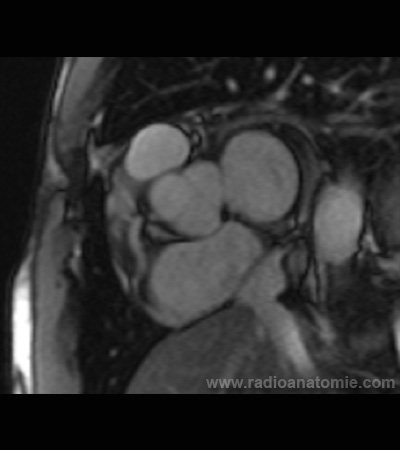

Radioanatomie et plans de coupe en IRM cardiaque

Plan de la valve aortique

Plan chambre de chasse du ventricule gauche (LVOT)

Plan 4 cavités

Plan 2 cavités

Artère pulmonaire

Oreillette droite

Oreillette gauche

Aorte descendante

Aorte ascendante